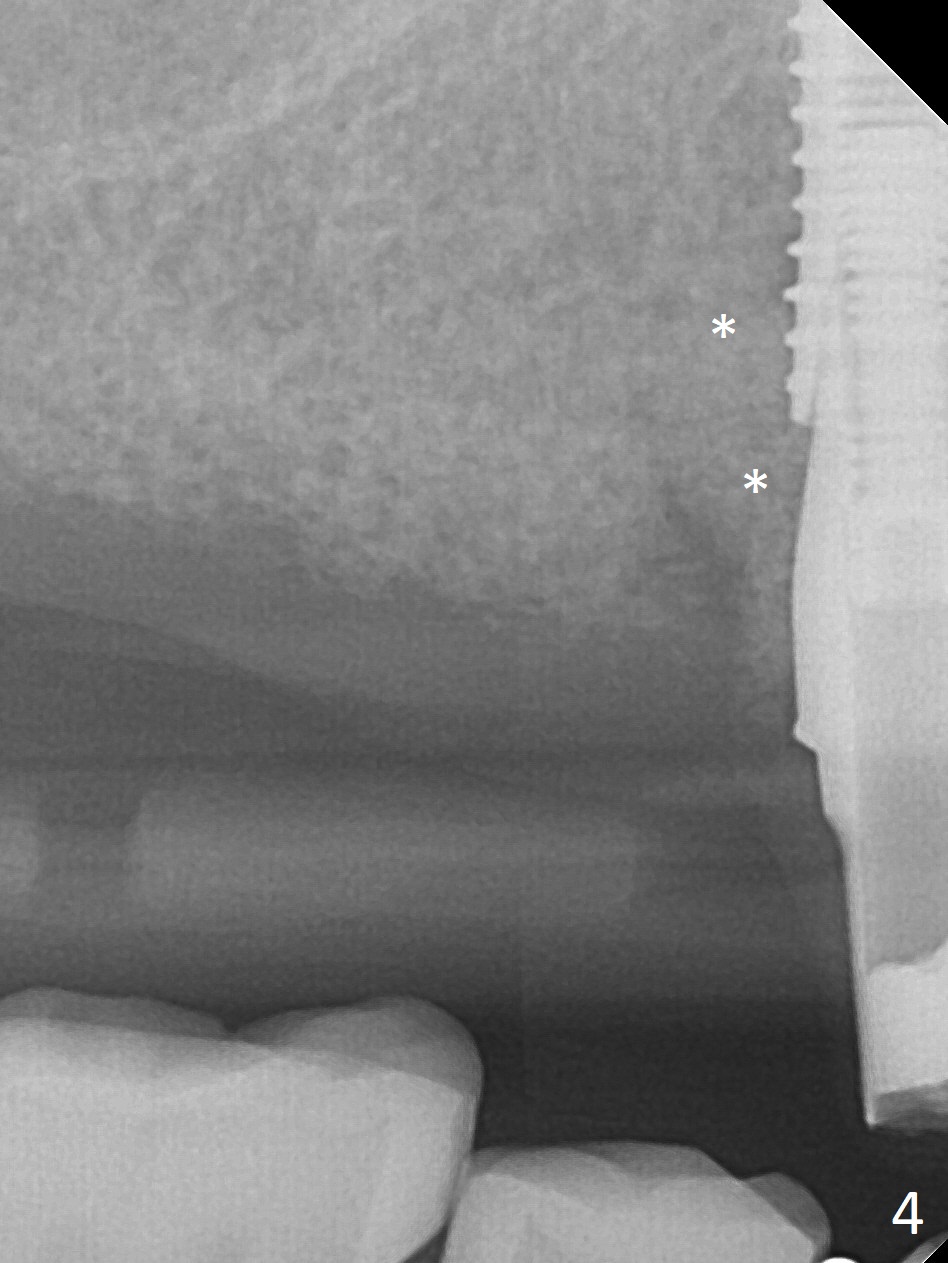

Extraction of the tooth #5 with mobility III reveals no buccal plate and low palatal plate. Osteotomy starts as palatal as possible (Fig.1). The bone density is low. After use of 2.7 mm drill (Fig.2), a 3 mm drill can be inserted into the osteotomy without resistance. A 4x16 mm implant is placed with insertion torque <30 Ncm. When an abutment is placed, the implant is found to have been placed distal. The implant is untorqued for change in trajectory. When a 4.5x7(5) mm abutment is placed, the abutment turns with the underlying implant (Fig.3). The former is kept to be turned with a hand driver until the latter is unable to turn. Following placement of allograft (Fi.g3,4 *), a mini-provisional is fabricated to retain the bone graft and at the same time not to be interfered with when a flipper is in and out. The bone graft in the former socket gap appears to have integrated into the native one 4.5 months postop (Fig.5).